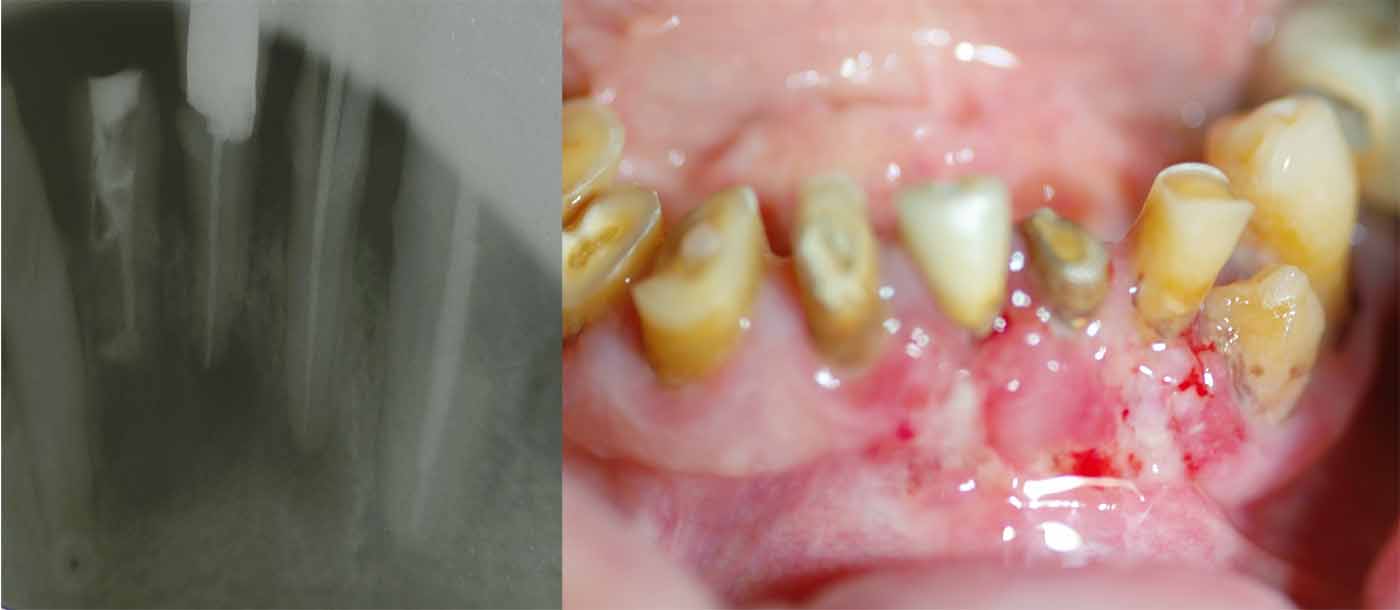

Ακολουθώντας τις πιο σύγχρονες τεχνολογικές εξελίξεις, έχουμε ενσωματώσει προηγμένα εργαλεία και μεθόδους στην ενδοδοντική θεραπεία. Χρησιμοποιούμε περιστροφικά εργαλεία τελευταίας γενιάς, σύγχρονα συστήματα έμφραξης με θερμοπλαστικοποιημένη γουταπέρκα, καθώς και ακριβείς συσκευές ανεύρεσης του μήκους των ριζικών σωλήνων, όπως το apex locator. Επιπλέον, η κλινική μας διαθέτει ψηφιακή ακτινογραφία και CBCT (αξονική τομογραφία) για την ακριβή διάγνωση και τον βέλτιστο σχεδιασμό της θεραπείας.

Ο συνδυασμός της τεχνολογίας με τη λεπτομερή προσέγγιση και την εξατομικευμένη φροντίδα που προσφέρουμε, μας επιτρέπει να επιτυγχάνουμε άριστα αποτελέσματα ακόμα και στις πιο απαιτητικές περιπτώσεις. Στόχος μας είναι η διάσωση των φυσικών δοντιών, διασφαλίζοντας τη μακροχρόνια υγεία και λειτουργικότητα του στόματος των ασθενών μας.